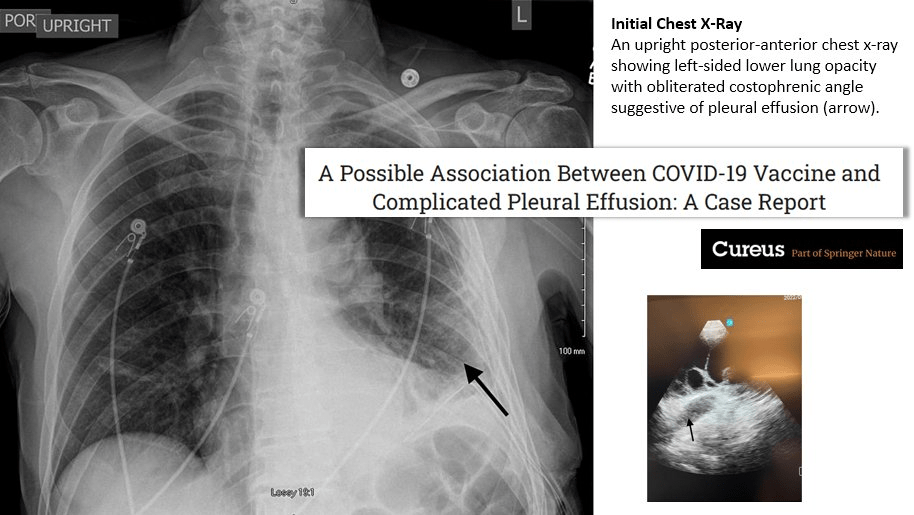

« Les cliniciens doivent être conscients que le vaccin COVID-19 est une cause sous-jacente possible chez les patients présentant un épanchement pleural qui reste autrement inexpliqué … » https://cureus.com/articles/156571-a-possible-association-between-covid-19-vaccine-and-complicated-pleural-effusion-a-case-report#!/

Epanchement pleural

Les cliniciens doivent être conscients que le vaccin COVID-19 est une cause sous-jacente possible chez les patients présentant un épanchement pleural qui reste autrement inexpliqué, que la causalité ne peut pas être établie dans ce cas et que les vaccins COVID-19 restent la pierre angulaire de la prévention de la maladie pour COVID-19. 19. Dans ce contexte, les étiologies infectieuses ne peuvent être totalement exclues. Les cliniciens doivent rester vigilants face à de telles possibilités, car l’établissement précoce du diagnostic et du traitement peut améliorer le résultat.